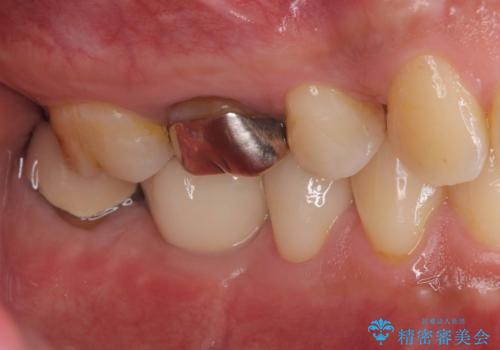

銀歯を除去後、やはり銀歯の下は虫歯になっていましたので、虫歯を除去した後にオールセラミッククラウンで被せました。

MOD窩洞のインレーは破折強度が弱くたびたび今回の症例のように歯が欠けてしまうケースがあります。破折ラインが歯根までいっていると抜歯となってしまう場合もあります。

破折から歯を守る為にはインレーよりもクラウンの方が優れています。